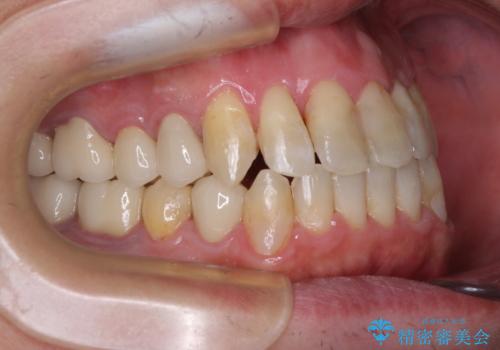

ワイヤー矯正を併用したことで、上顎前歯はあっという間に整いました。

補綴治療にあたり、痛みのある歯に対して根管治療を行うこととしましたが、処置が必要な歯が多かったため、期間を要しました。

補綴治療中に前歯のデコボコが戻ってしまったため、補綴治療後にインビザラインを1セット追加して仕上げました。